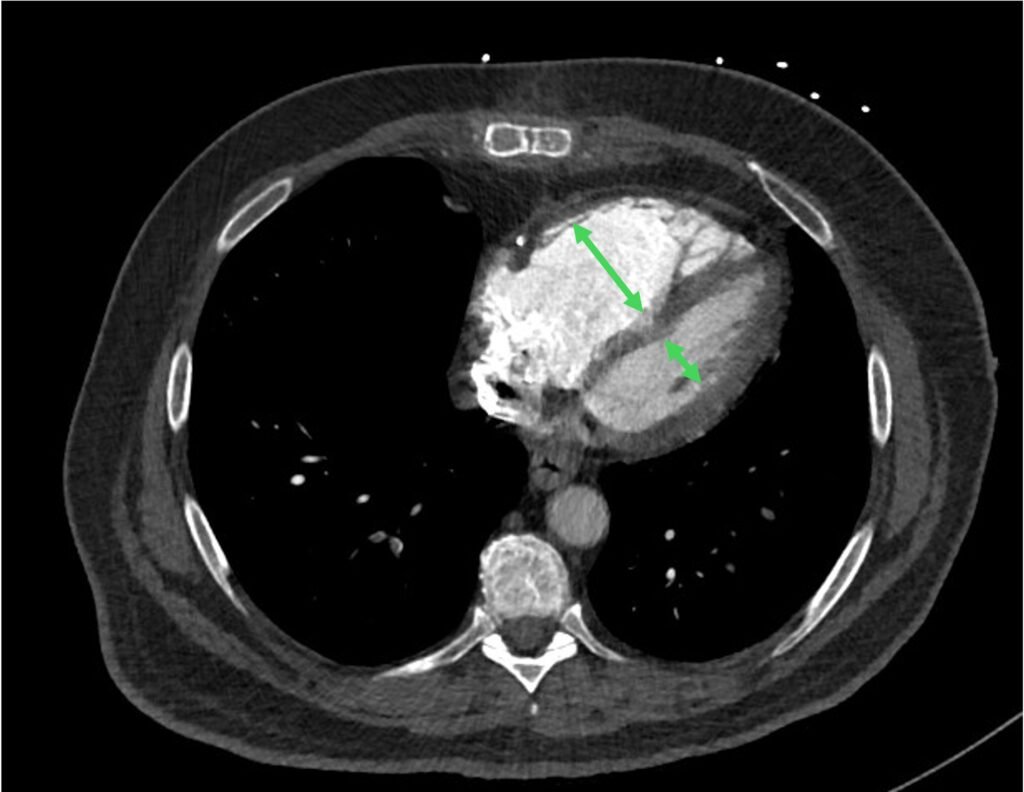

When the clot burden is high, it can often put a strain on the RV. This is really one of the things that you don’t want to miss. Main features includes:

- enlarged RV with RV:LV ratio > 1

- flatenning or bowing of the intraventricular septum

Figure 9: enlarged RV with RV:LV ratio > 1

Figure 10: flattening / bowing of the intraventricular septum